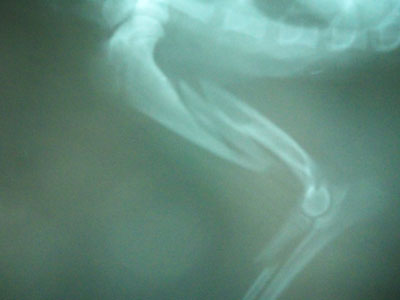

ΗΜΙΑΙΜΟ ΣΚΥΛΑΚΙ ΜΑΥΡΟΑΣΠΡΟ 8 ΜΗΝΩΝ.

20 ΗΜΕΡΩΝ ΚΑΤΑΓΜΑ ΑΡΙΣΤΕΡΗΣ ΚΕΡΚΙΔΑΣ ΠΛΗΡΕΣ ΛΟΞΟ ΧΩΡΙΣ ΚΑΤΑΓΜΑ ΤΗΣ ΩΛΕΝΗΣ. ΤΟ ΟΠΟΙΟ ΘΑ ΑΝΤΙΜΕΤΩΠΙΣΤΕΙ ΣΥΝΤΗΡΗΤΙΚΑ. ΚΑΙ ΚΑΤΑΓΜΑ ΑΡΙΣΤΕΡΟΥ ΒΡΑΧΙΟΝΙΟΥ.ΤΜΗΜΑΤΙΚΟ ΣΤΟ ΑΝΩ ΤΡΙΤΟ ΤΗΣ ΔΙΑΦΥΣΗΣ .